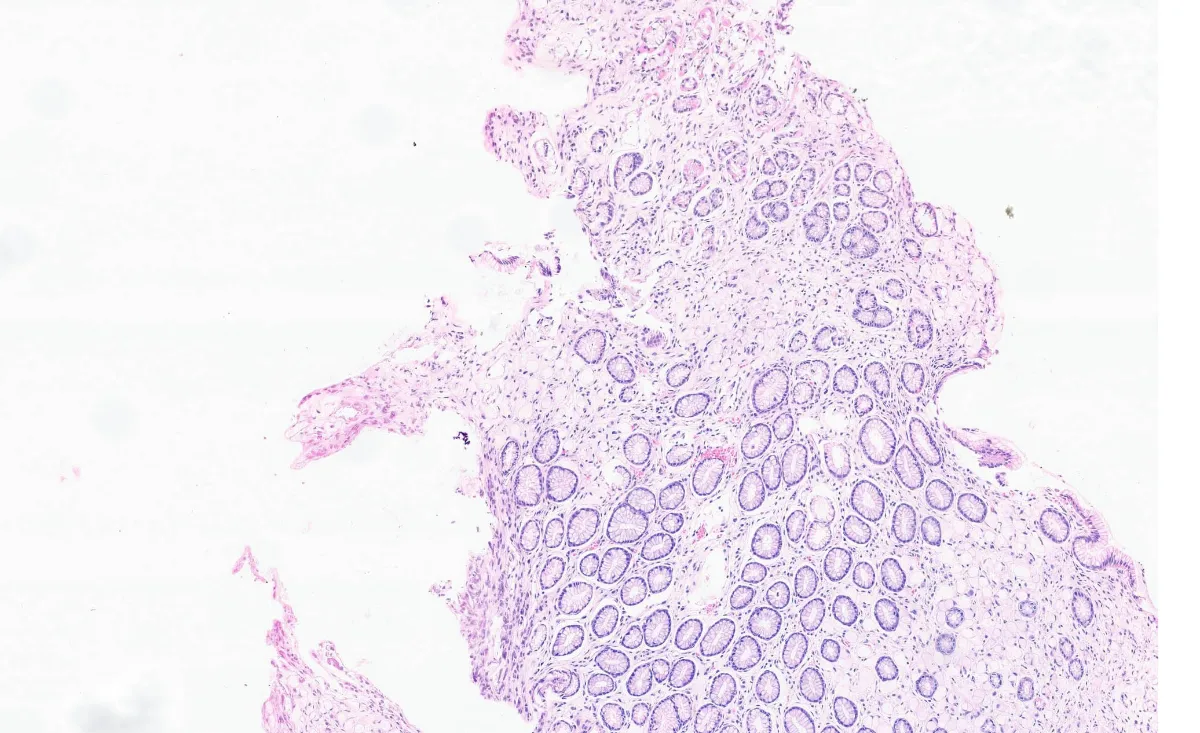

1. BIOPSIA HE X200

4. GASTRECTOMÍA HE X100